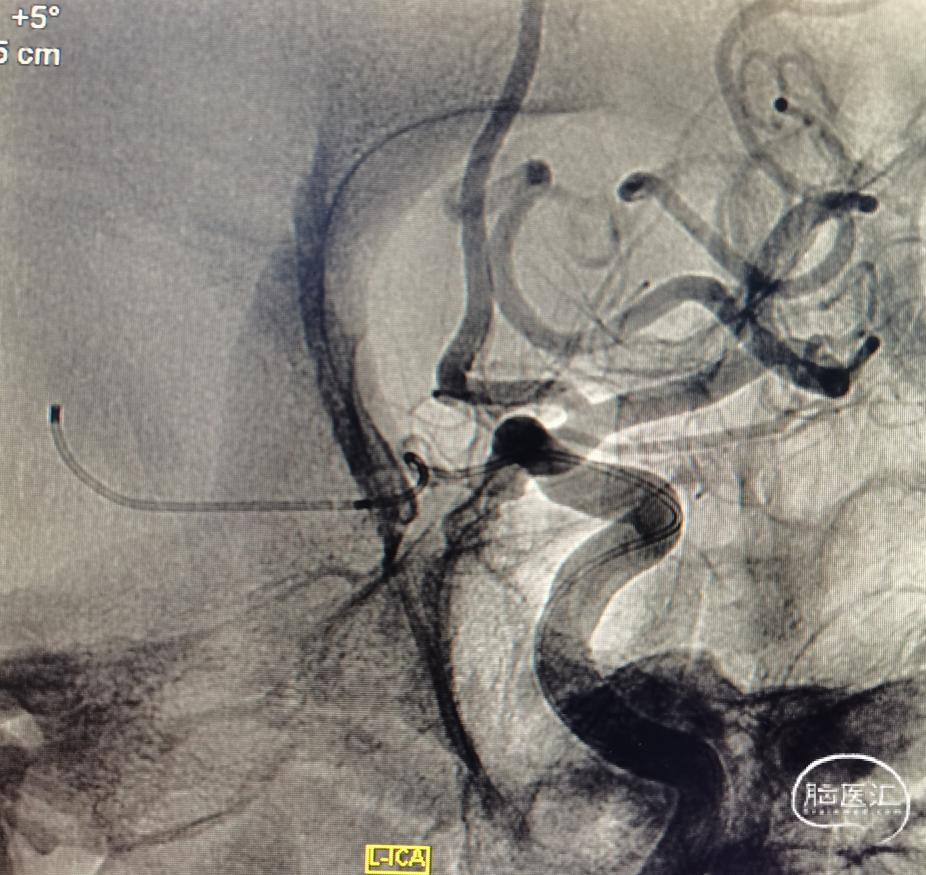

简单看看,还行。患者辗转到位,还是先安排一下造影吧。于是直接造影。原来跟我们评估的差不多,还是左侧后交通动脉瘤。

正如先前提到,瘤不大,需要精准微导管塑型。胚胎大脑后动脉,因此,载瘤动脉还是需要保的。于是乎,左选选,右选选。到底选啥支架那?利用弹簧圈微导管输送的支架,没货。所以只有选择普通支架输送的微导管。因此问题来了,如果用普通的支架微导管,直径比较粗,因此当进入后交通动脉时,导管张力特别大,有顶破动脉瘤的风险。所以,没有可选,直接微导管交换三米支撑导丝,把支架导管输送上去。

三米交换导丝,顺利到位。就看支架导管得了。既往有过顶破的经历,因此特别小心。好在三米支撑导丝的支撑能力比较好。但是也是一点一点的调整支架导管的位置,好在一切努力没有白费,支架导管一点一点越过后交通动脉起始,慢慢爬过过度弯曲之处。好在导管还能前行一些,紧绷的心终于放下了。起码离成功还有一半。于是就是弹簧圈微导管的到位,塑了个“猪尾”,第一次角度稍微大了一点点。如图。到位还算容易。也没有想太多,直接就用最小的圈,先把瘤填上,防止再次出血,可是现实并没有那么容易。